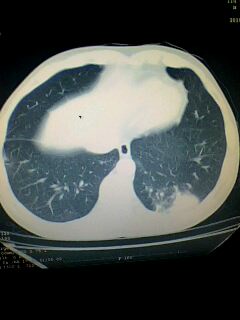

标题: CT28315:咳嗽咳痰咯血半月并胸痛 [打印本页]

标题: CT28315:咳嗽咳痰咯血半月并胸痛

1、纵膈窗效果不好,初步考虑左肺下叶感染性病灶,建议正规抗炎治疗后复查   2、右肺下叶陈旧性病灶伴局部胸膜增厚。

考虑左肺下叶周围型肺癌.图象欠清,请问病人贵更?

考虑左肺下叶周围型肺癌.

左下肺肿块影,深分叶,考虑肺癌。

左肺下叶球形肺炎,建议抗炎治疗后复查

左下肺球形病灶,考虑:1:球形肺炎;2:周围型肺癌不除外,建议治疗后复查